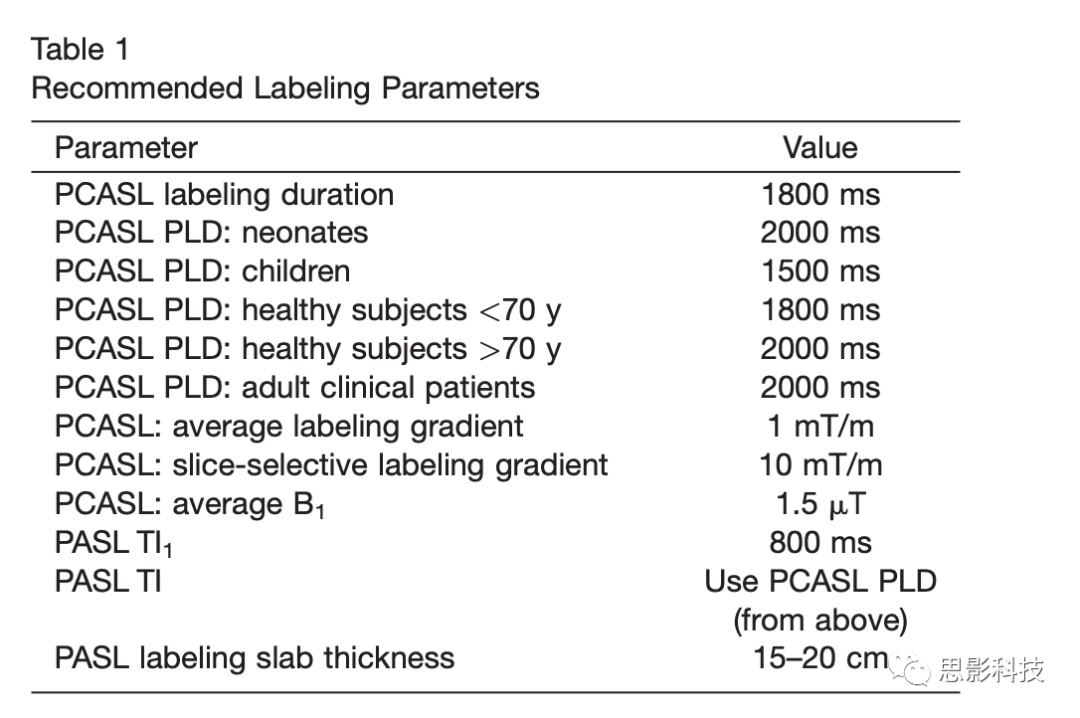

最佳标注持续时间取决于标注的弛豫时间,还取决于标注持续时间对重复时间的影响。 ASL信号随着标注持续时间的增加而增加,但随着标记持续时间的增加,返回信号的衰减比血液的弛豫时间长得多。较长的持续时间会增加单次的扫描时间,从而减少单位时间内获得图像的数量。当ATT长到4s这样的长度时,持续时间可能会提高信噪比,并有助于保留信号。但是,较长的标注持续时间会增加对组织T1的信号依赖性,并且由于功率沉积和背景抑制约束而可能无法实现。由于缺乏长时间的临床标注经验,因此本文推荐采纳表1中标注时间为1800毫秒的采集方案,这是在T1敏感性以及临床经验限制的情况下有效提高信噪比,并在临床应用asl技术的折衷方案。

单PLD采集方法

使用PCASL进行CBF量化,理想情况是将PLD设置为刚好大于对象中存在的动脉传输时间的最长值。在这些条件下,整个标记的大剂量血液在图像采集之前被传送到组织,并且CBF测量将因不完全的传送而无畸变。由于ASL信号在标记后随时间常数T1衰减,因此就信噪比而言,代价太高,以至于在选择PLD时过于保守,研究者要求在任何情况下都要严格保证PLD比动脉转移时间长。在健康灰质中,根据标注定位的不同,其动脉传输时间大约在500到1500ms之间。但是在某些脑血管疾病以及深部灰质中,动脉传输时间则会大于2000ms。因此PLD的选择根据对信噪比的要求以及扫描范围的大小,以保证大脑CBF的精确测量为前提作折衷选择。而且也要意识到ASL信号较弱的区域可能不单单是脑血流量低的结果,而有可能是较低的脑血流与不寻常的长动脉传输时间共同作用导致的。一些情况下标注过的自旋血液滞留在动脉之中也会到导致动脉传输时间的延长。而这种情况与人的年龄关系较大,越发高龄的被试中这种情况越发常见。因此PLD的选择也需要根据被试年龄作适当调整。在表1中列举了推荐的PLD数值,其中针对于成年患者的临床使用可用2000ms的PLD,该参数相对独立于年龄,且在各种各样的未知的疾病中也同样适用。

基于上述分析,使用单个PLD的PCASL是可以稳定直接采集脑血流的方法,因此也是在临床应用上推荐的标准方案。而待QUIPSS-Ⅱ修正的PASL类似于PCASL可以很好地确定标注后的持续时间,并允许在单个TI的条件下量化CBF。但是由于PASL信噪比过差,我们推荐在PCASL无法使用的情况下使用PASL。对于带QUIPSS-Ⅱ修正的PASL推荐TI应该设置在800ms,具体的设置参数可参考表1。需要注意的是 PCASL中的PLD与PASL中TI的定义是类似的。这有效地导致PASL的TI比PCASL短800ms。虽然这并不理想,因为它增加了不完全标记血液输送到PASL成像区域的可能性,但它也增加了信噪比,被认为是弥补PASL固有的低信噪比的必要权衡。另外通过降低图像的分辨率来保证信噪比也是一种可行方法,但是其还未在临床做过测试。